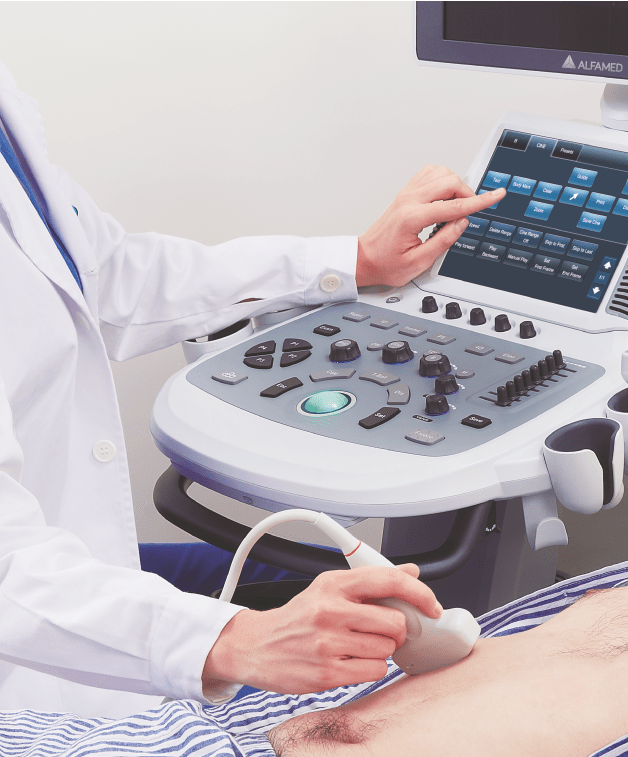

Dotado de softwares avançados e transdutores específicos, o Magnus X5 apresenta alta versatilidade para imagem geral e excelente performance, principalmente, nos exames de cardiologia avançada e obstetrícia.

Possui design robusto, tela principal e tela touch screen de dimensões adequadas para melhor visualização da imagem e fácil manejo, painel de controle com ajuste de altura e rotação, favorecendo a ergonomia no momento do trabalho do profissional.